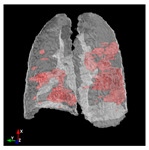

In Table 6, a comparison of the ground truth and prediction results of each model is presented in 2D, along with the 3D projection of each model. The visual analysis of the predictions provides additional insights into the performance of each model. The visualizations demonstrate that Attention UNet captures the intricate details of the lung construction more accurately, resulting in more precise segmentation of the infected areas compared to other models.

Table 6.

Comparison of ground truth and model prediction results using UNet, LinkNet, Attention UNet, UNet 3+, and TransUNet.

Attention UNet stands out due to its sophisticated attention mechanisms that allow it to focus on relevant regions and features within the lung structures. This characteristic enhances its ability to capture intricate details specific to COVID-19-affected lungs. The attention mechanisms contribute to Attention UNet’s impressive IoU score of 85.36% and dice score of 91.49%, showcasing its potential to provide accurate and finely detailed segmentations. The results suggest that its trait of dynamically assigning different weights to regions, based on their contextual importance, is instrumental in achieving precise and meaningful segmentations in complex medical images.